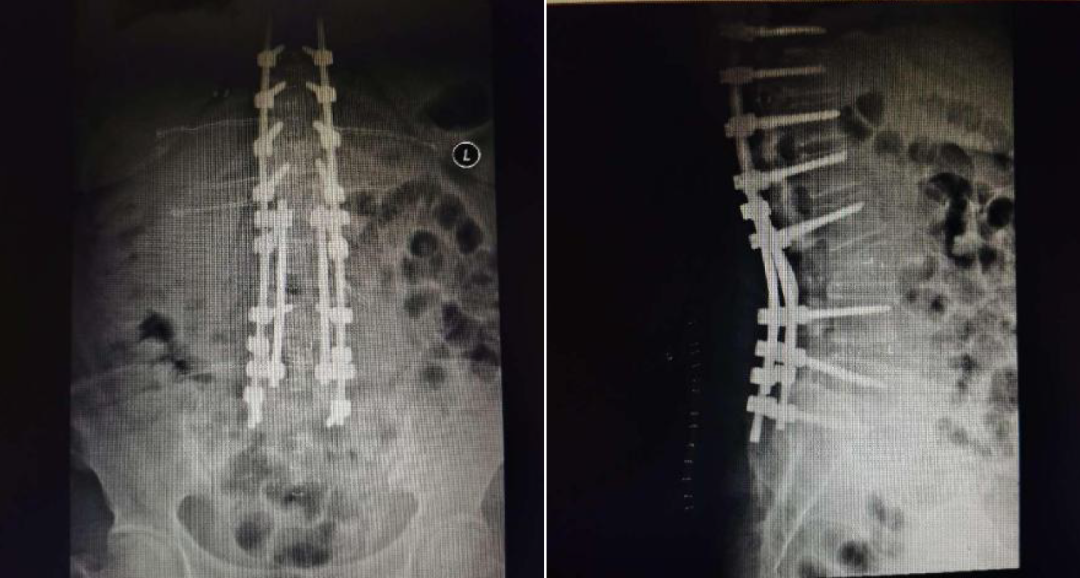

脊柱矯形術(shù)后效果

德康醫(yī)療——脊柱畸形去旋轉(zhuǎn)類方案

北京協(xié)和醫(yī)院仉建國(guó)教授團(tuán)隊(duì)合作研發(fā)的VSS脊柱專用矯形器械,功能強(qiáng)大,靈活應(yīng)對(duì)脊柱復(fù)雜三維矯形手術(shù)。

VSS惟德矯形系統(tǒng)器械常搭配單平面螺釘用于脊柱旋轉(zhuǎn)畸形患者的去旋轉(zhuǎn)操作 VSS惟德矯形系統(tǒng)器械分5.5系統(tǒng)和6.0系統(tǒng)

脊柱側(cè)彎畸形,椎體不在一條力線上,使用多米諾旁開一根棒 脊柱畸形患者身高還在增長(zhǎng)情況下的生長(zhǎng)棒技術(shù) 翻修患者的棒延長(zhǎng)脊柱側(cè)彎畸形,椎體不在一條力線上,使用多米諾旁開一根棒 脊柱畸形患者身高還在增長(zhǎng)情況下的生長(zhǎng)棒技術(shù) 翻修患者的棒延長(zhǎng)